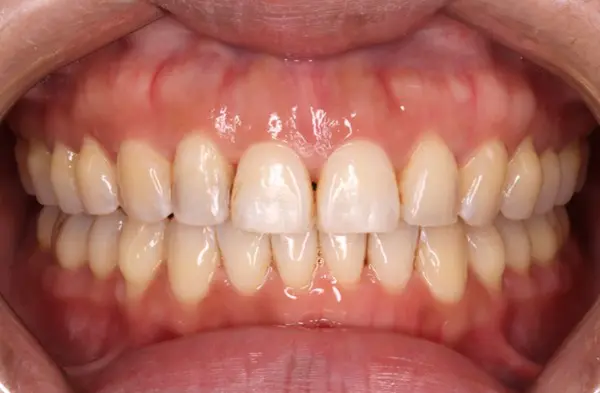

Crowding

After